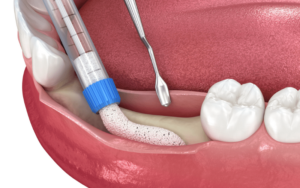

An endosteal implant is made comprised of an artificial tooth root that is inserted directly into the jawbone. Find out if you are a good candidate for dental implants. The implant protrudes through the gum, with the abutment and crown sitting on top. Endosteal implants serve an important role in improving dental health by slowing jawbone degradation. When a tooth is lost, the surrounding jawbone gradually deteriorates. Endosteal implants operate as a prosthetic tooth root, promoting bone regeneration while efficiently preventing additional bone loss, providing long-term stability. More specifically, the benefits include:

- Endosteal implants provide an exceptionally stable base for replacement teeth by being directly anchored into the jawbone. This secure integration closely mimics the natural tooth root, enhancing chewing, speaking, and overall oral function with remarkable reliability.

- By replacing the tooth root, endosteal implants actively prevent bone loss in the jaw. Tooth loss often triggers jawbone deterioration, but these implants stimulate bone regeneration, safeguarding long-term oral health and structural integrity.

- Crafted from biocompatible materials like titanium, endosteal implants are built to last. Their high compatibility with the human body minimizes risks, offering a durable, long-term solution for tooth replacement needs.